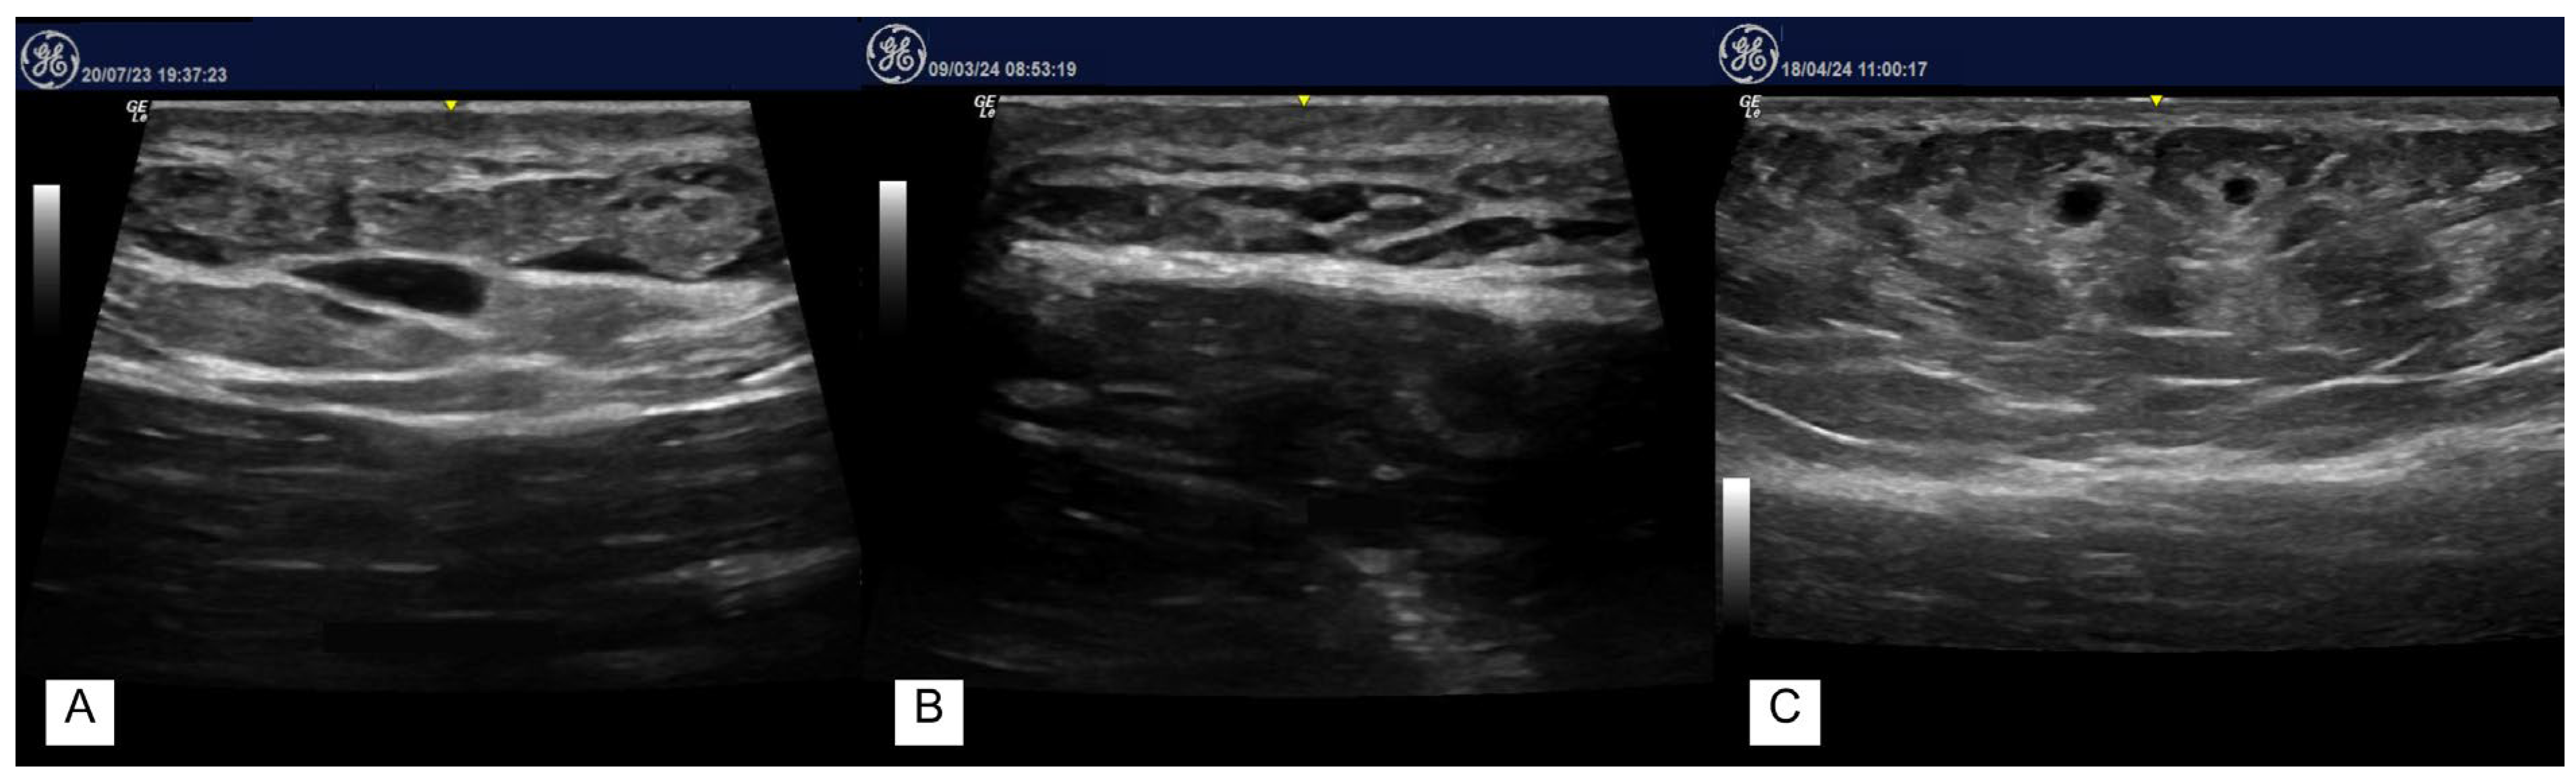

3. Results